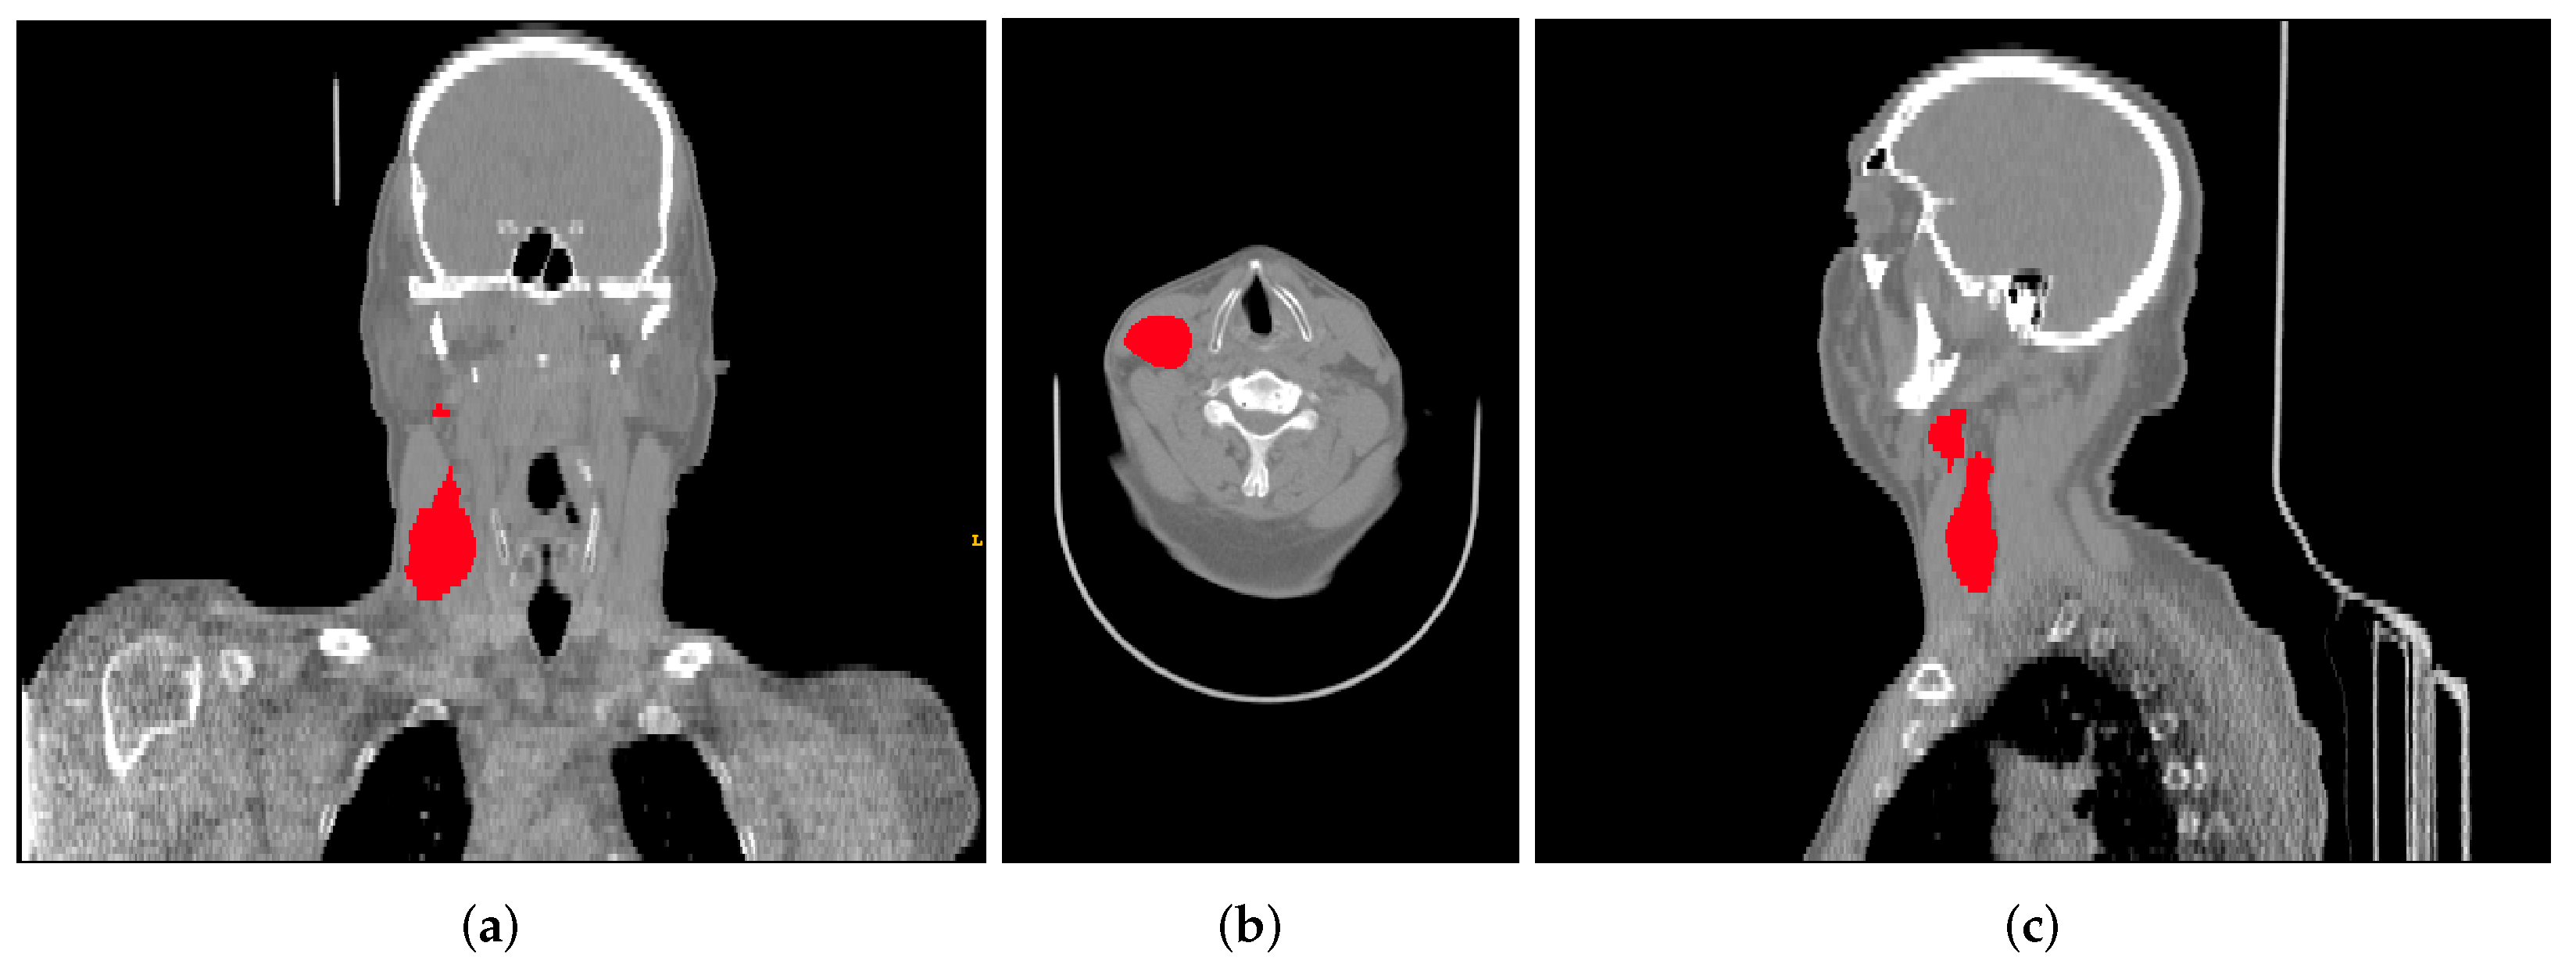

This data collection contains FDG-PET/CT pre-treatment scans (Figure 2) with a median of 18 days (range: 6–66) before treatment, clinical information (sex, age, primary site, cancer stage, HPV status, among others), and the radiotherapy structure set, plan, and dose, respectively, RTStruct, RTPlan, and RTDose. Part of the tumour segmentation was performed directly on the CT scan of the hybrid PET/CT scanner by oncologists specialized in radiotherapy and used for treatment planning. However, in most cases, the tumour was segmented in a separate CT scan for therapeutic planning and, through the software MIM (MIM software Inc., Clevant, OH, USA), was projected on the FDG-PET/CT scan.

Figure 2. Example of a CT scan from the data collection with the corresponding segmentation of the gross tumour volume, shown in all three planes: (a) coronal, (b) axial, and (c) sagittal.